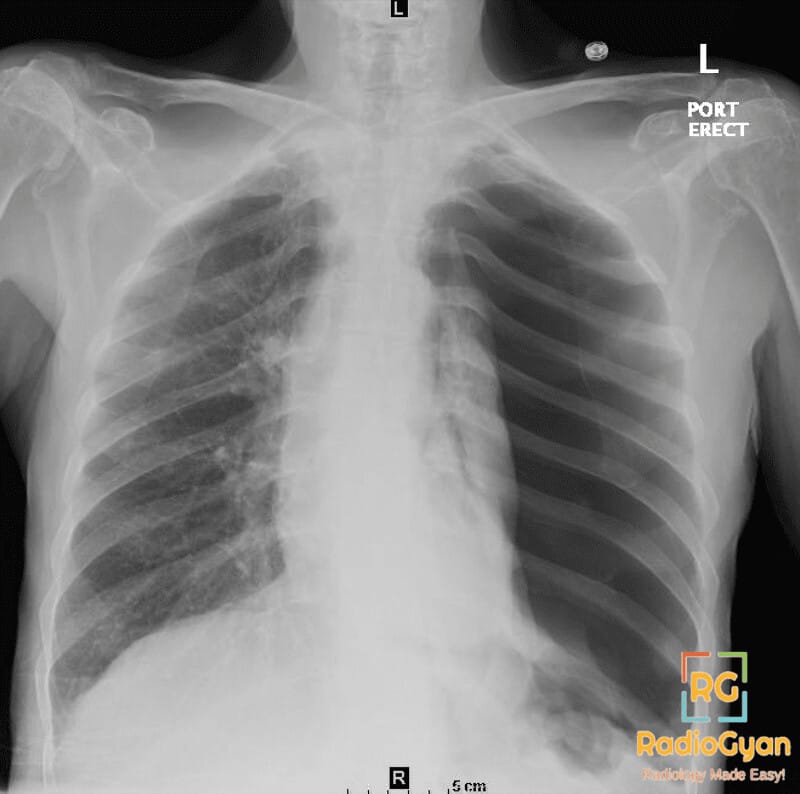

Chest radiograph showing left sided tension pneumothorax

Chest radiograph showing left sided tension pneumothorax with mediastinal shift

• Radiograph: Key findings include ipsilateral hypertransradiancy, lung collapse, mediastinal shift away from the affected side, depressed diaphragm, and splayed ribs.

• Signs: Deep sulcus sign (depressed diaphragm) and sail sign (mediastinal shift) are notable radiological signs.